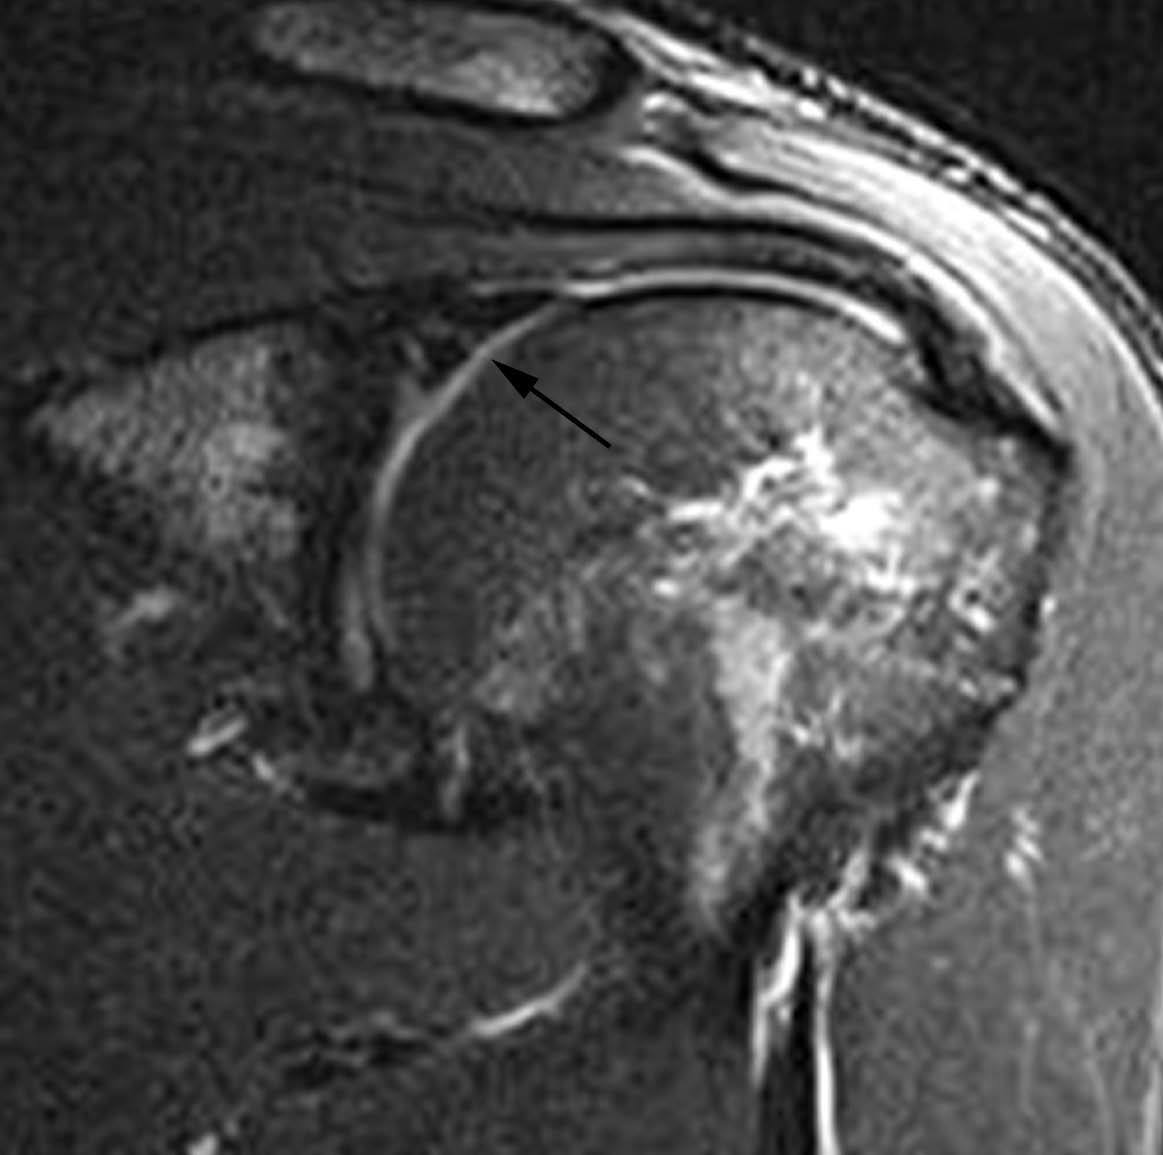

Lesiones por pinzamiento posterosuperior (posterosuperior impingement syndrome) < del LG superior con extensión posterior (SLAP tipo II-b), roturas parciales o completas del tendón del supraespinoso y pequeñas fracturas por compresión del margen posterosuperior del trocánter. Estas lesiones se producen típicamente en el atleta lanzador.

La etiología y el mecanismo de producción de estas lesiones han sido ampliamente debatidos. Jobe et al en 198930 consideraron que estas lesiones eran debidas a una laxitud de la cápsula anterior que producía una migración anterior de la cabeza humeral durante la abducción y rotación externa. En 1991, Walsh et al31, siguiendo la teoría de Jobe et al30, describieron el síndrome de pinzamiento interno o posterosuperior relacionado con una laxitud capsuloligamentosa anterior. En 1998, Burkhart et al describieron una alta incidencia de SLAP II-b en el atleta lanzador32. Estos mismos autores llegaron a la conclusión en el año 200333 de que las lesiones descritas anteriormente son producidas por una cascada de eventos originados por una fibrosis y engrosamiento de la cápsula posteroinferior y de la banda posterior del LGHI. Según estos autores, el atleta lanzador, después de múltiples movimientos de abducción y rotación externa, consigue un desplazamiento del punto de rotación y del arco de traslación del trocánter desde el centro de la cavidad glenoidea hacia arriba y hacia atrás «la zona» tal como se describe anteriormente (microinestabilidad). Todo ello conduce a un engrosamiento de la cápsula posterior que evoluciona a una restricción de la rotación interna (fig. 34). A esta restricción se la considera el punto de origen de la cadena de lesiones que conducen a lo que se llama el «brazo muerto» (the dead arm) que representa el final de una carrera profesional deportiva. La restricción de la rotación interna se la conoce bajo las siglas de GIRD (glenohumeral internal rotation deficit). Sin embargo, no queda claro si la traslación posterosuperior del centro de rotación en el atleta sucede antes o después de la formación de cicatriz y engrosamiento capsular posterior.

Cuando el deportista consigue crear, a través del entrenamiento, este desplazamiento posterosuperior del centro de traslación o bien tiene lugar a través del engrosamiento de la cápsula posteroinferior, el hombro llega a conseguir una rotación externa de más de 150 grados en abducción a 90 grados. En este momento se llega a un punto crítico, en el cual la tensión que se produce a nivel de la inserción del TLB, en el borde superior del LG, conduce a un «arrancamiento» del mismo, con extensión de la lesión hacia la parte posterior (SLAP II-b); a este mecanismo se le conoce como peel back (fig. 35).

Una vez que se ha producido la lesión SLAP II-b, la continuación de las fuerzas de extrema rotación externa conducen a una torsión repetitiva del tendón supraespinoso, que lleva a una rotura parcial o completa del mismo (fig. 36).